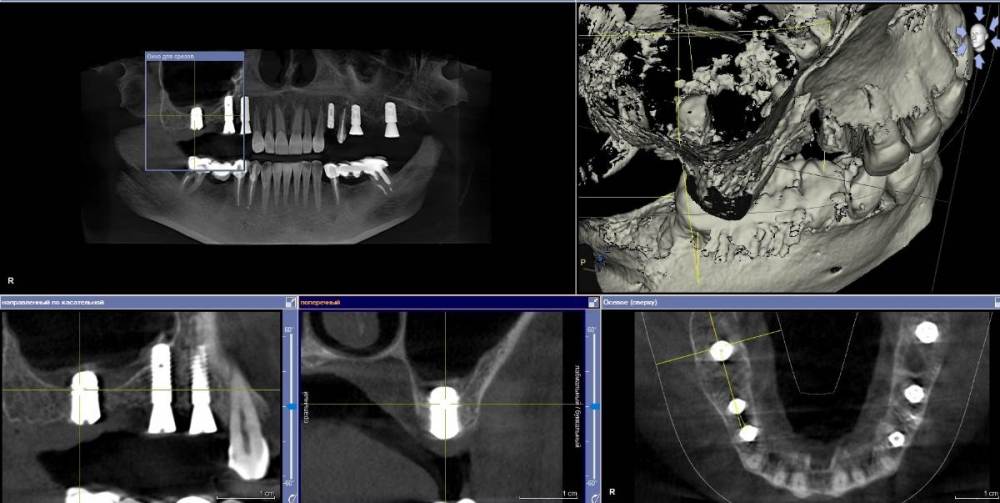

Ponchik Опубликовано 12 сентября, 2021 Поделиться Опубликовано 12 сентября, 2021 Избегаем пазухи. 14- штрауманн бон левел 3.3-10 15- штрауманн бон левел 3.3-10 17- штрауманн тишью левел 4.8-6 18- штрауманн тишью левел 4.8-8 Вопрос знатокам. А нужен ли в области 1.8? Или я перестраховываюсь? Ссылка на комментарий

Ponchik Опубликовано 19 сентября, 2021 Автор Поделиться Опубликовано 19 сентября, 2021 17.09.2021 в 22:03, stommm сказал: 17 8 мм wn без 18. Думаю более чем достаточно будет Но шаблончик я на 18 сделал тоже (на всякий) Пока только слева установил 4 2 Ссылка на комментарий